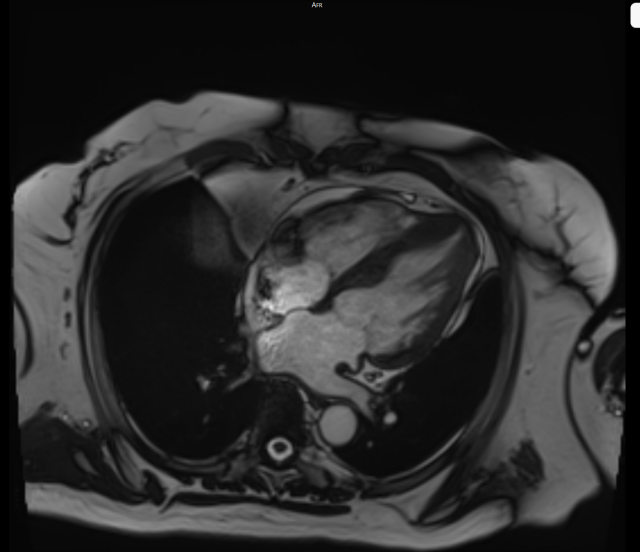

技术名称:心脏磁共振成像(Cardiovascular Magnetic Resonance, CMR),简称心脏核磁

心脏核磁是目前心血管疾病诊断领域无创、无辐射、精准度极高的核心影像学技术,依托磁共振多序列、多参数成像原理,可清晰呈现心脏的解剖结构、心肌形态、心功能状态、心肌血流灌注及心肌活性等关键信息,被业界誉为评估心脏结构与功能的“金标准”。

该检查无需穿刺、无电离辐射,安全性高,能为临床提供全面、定量的心脏评估数据,为心血管疾病的早期诊断、精准分型、疗效评估及预后判断提供可靠依据,是现代心血管诊疗的重要技术支撑。